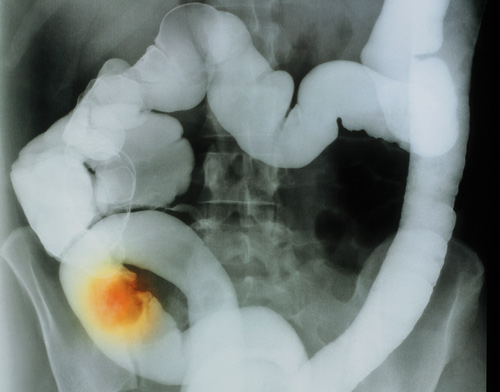

De som overlever kreft i barneårene, har økt risiko for gastrointestinalcancer, mest i colon og rectum. Dette gjelder særlig etter visse former for kreft og kreftbehandling.

14 358 personer som var blitt behandlet for kreft før fylte 21 år ved 26 sykehus i USA og Canada, ble kontaktet minst fem år etter at den første kreftdiagnosen ble stilt (median 22,3 år) (1). 45 hadde utviklet gastrointestinal cancer, mot forventet ni (standardisert insidensratio (SIR) = 4,6; 95 % KI 3,4 – 6,1).

Risikoen var høyest hos dem som hadde hatt Hodgkins lymfom eller Wilms tumor eller var blitt behandlet med abdominal røntgenterapi, procarbazine i høye doser eller platinaholdige legemidler. Forfatterne anbefaler tidligere screening for tykktarmskreft for dem som har overlevd kreft i barneårene enn det som anbefales for normalbefolkingen.